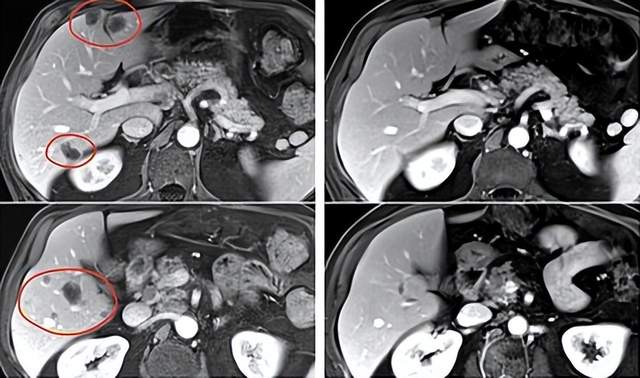

在接受TIL疗法和帕博利珠单抗治疗10个月后,一名直肠癌患者肝转移病灶大幅缩小。